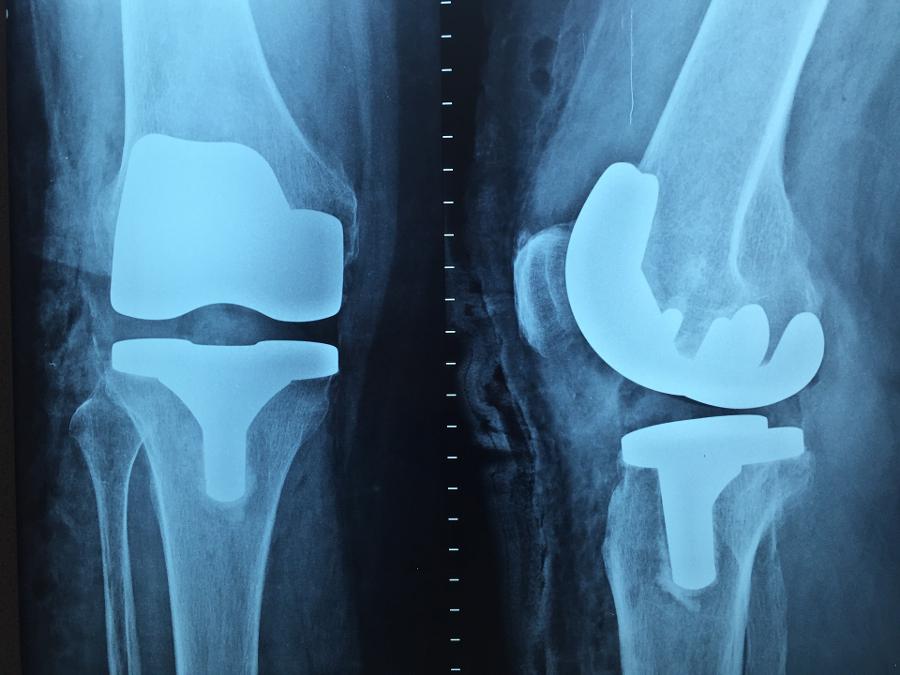

Ο ορθοπαιδικός χειρουργός Μιχαήλ Δαγιακίδης αναλαμβάνει ορθοπαιδικές παθήσεις και επεμβάσεις όπως παθήσεις ώμου (ασβεστοποιός τενοντίτιδα, αστάθεια ώμου, εξάρθρημα ώμου, παθήσεις ακρωμιοκλειδικής άρθρωσης, παθήσεις του τένοντα του δικεφάλου βραχιονίου, ρήξη ανώτερου επιχείλιου χόνδρου, ρήξη στροφικού πετάλου του ώμου, συμφυτική θυλακίτιδα, σύνδρομο πρόσκρουσης ώμου, σύνδρομο υπακρωμιακής πρόσκρουσης), επεμβάσεις ώμου (αρθροσκόπηση ώμου), παθήσεις γονάτου (βλάβες αρθρικού χόνδρου γόνατος, εξάρθρημα επιγονατίδας, ρήξη μηνίσκου, ρήξη οπίσθιου χιαστού, ρήξη πρόσθιου χιαστού, τενοντοπάθεια επιγονατικού τένοντα), επεμβάσεις γονάτου (αρθοσκόπηση γόνατος, αρθροπλαστική γόνατος, κατάγματα μηριαίων κονδύλων, κατάγματα κνημιαίων κονδύλων, κάταγμα επιγονατίδας), ισχίο (ολική αρθροπλαστική ισχίου, διατροχαντήριο κάταγμα ισχίου, υποκεφαλικό κάταγμα ισχίου) κ.α.